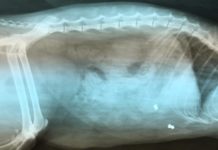

Ktoś strzela z wiatrówki do zwierząt

Na osiedlu Ustronie nieznana osoba strzela z wiatrówki do zwierząt. Ranny został co najmniej jeden kot, który trafił do weterynarza.

Na portalu społecznościowym na stronie...